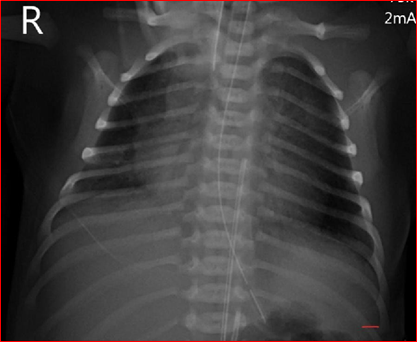

The x-ray (Figure 1) confirmed the position of the both lines at thoracic vertebra 7 levels (T 7) for the UAC and thoracic vertebra 10 level (T10) for the presumed UVC. The X- ray included the chest only and hence the whole courses of both catheters were not identifiable. However, they both looked heading toward the left side of the vertebrae. Dextrose 10% was infused through the lower central line which is presumed to be UVC, while antibiotics were given through peripheral venous line as per the neonatal unit policy.

Figure 1 (First X-ray: Two vascular catheters were identified with the tips positioned at level T7 and T10 thoracic Vertebrae, The view did not include full course of the catheters).